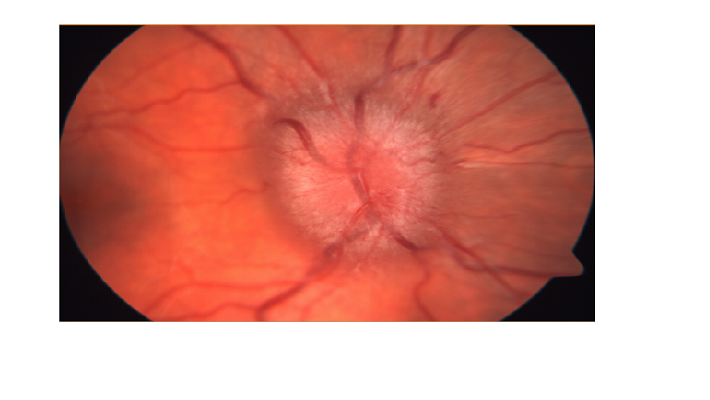

במקרים בהם יש חשד לעלית לחץ בראש, רופא העיניים יכול לאבחן את הבצקת בעצבי הראייה הנקראת פפילאדמה (PAPILLEDEMA).

בתמונה: בצקת בעצב הראייה הנגרמת בשל לחץ תוך גולגלתי מוגבר